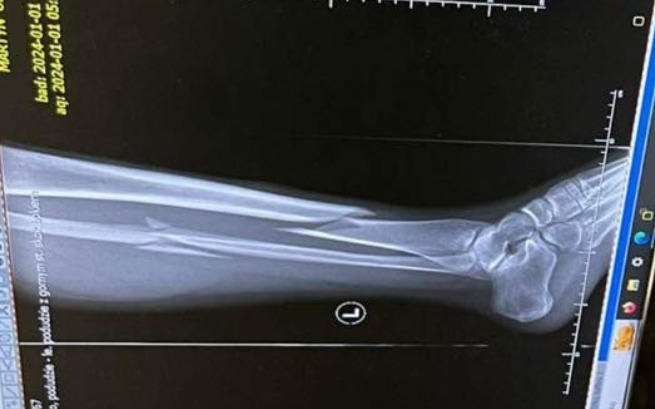

Podniosłam nogę i zobaczyłam, że piszczel nienaturalnie się zgina. Karetka przewiozła mnie do szpitala i jeszcze tego samego dnia przeszłam operację. Złamaniu uległa kość strzałkowa i piszczelowa. Lekarze wstawili mi gwóźdź ryglowany śródszpikowy.

Wszystko stało się 1 stycznia. Dziś noga na szczęście się zrasta, miałam już wyciągniętą śrubę i teraz staram się powoli wrócić do sprawności. Od fizjoterapeuty wiem, że nie ma na co czekać i już teraz najlepiej zacząć rehabilitację.